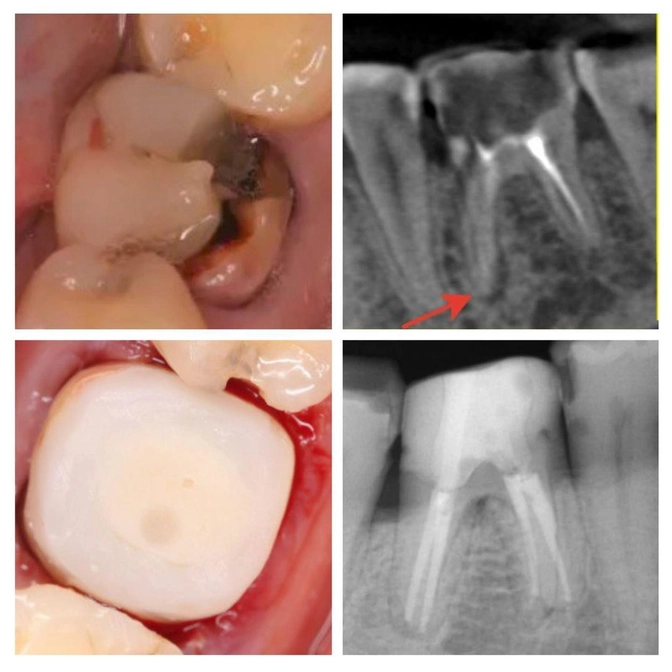

Покажу вам случай из практики Галины Базылевой, нашего терапевта эндодонтиста.

Пациент взрослый.

Зуб шестой.

Как выглядел до лечения, посмотрите на фото.

Особое внимание обращаю на то, что зуб и его корни маленькие по сравнению с соседними.

Потому что он был пролечен еще в детстве и это повлияло на его формирование.

Что сделано

✔️Зуб распломбирован

✔️каналы тоже распломбированы, пройдены, промыты, высушены.

ЕСТЕСНО! Под микроскопом

Кстати, тут ещё и анатомия зуба не подкачала.

Вместо стандартных двух корней, целых ЧЕТЫРЕ!

✔️Доктор Базылева нашла и пролечила каждый миллиметр;

Заново «собрала» зуб как конструктор

✔️Укрепила зуб стекловолоконным штифтом;

✔️Проконтролировала заполнение каналов с помощью снимка;

✔️Восстановила зуб билдапом (недавно был пост о нем)

В таком виде передаем пациента в руки ортопеда для изготовления коронки.

Зуб спасли!